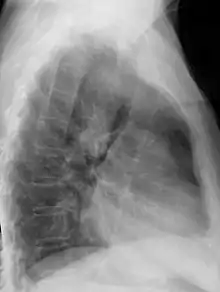

| Anterior-posterior chest radiograph showing a right-sided aortic arch |

After birth, a right-sided aortic arch is visualized on chest radiography, by the aortic knob (the prominent shadow of the aortic arch) that is located right from the sternum instead of left. Complex lesions are often assessed by MRI or CT.